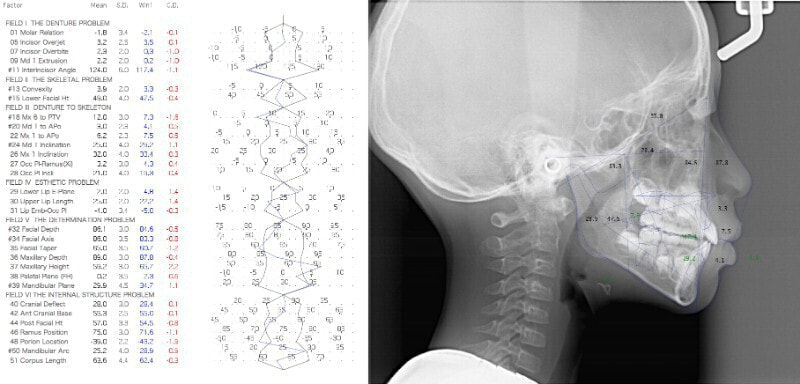

分析診断:FXフェイシャルアキシスが83度で、咬合力が極端に弱い顔面骨格ではありません。上下顎の骨格的バランスも平均値内には収まっています。Upper Molar PTV値から、上顎の奥行きが少ないとわかります。前歯の位置、E-lineと下唇の位置等から、歯が大きくて顎が小さいディスクレパンシーケースであると診断されます。

分析診断:左右の骨格的非対称が少し認められます。上顔面の幅径はさほど狭くなありませんが、下顎や下顔面の幅径は狭いと出ています。